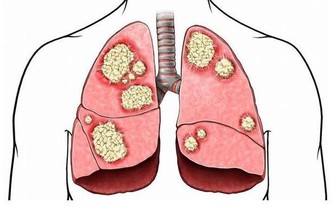

要想知道吃酸味食物會不會影響骨骼發育,建議大家先來看看骨頭的構成。

骨質的成分主要有兩類,一類是有機成分,另一類是無機成分。

有機成分一般是指骨頭里面的細胞、膠原蛋白質、纖維及血管組織等,這些成分賦予骨的彈性和韌性;

無機成分是指構成骨的一些礦物質,主要是使骨骼堅硬結實的鹼性磷酸鈣鹽。

正常情況下,骨的有機成分和無機成分各佔一定的比例。適當的比例能使骨頭既堅硬又柔韌,既不會出現“軟骨頭”的情況,也不會出現骨頭像玻璃那樣很硬,但同時也很脆弱,一碰就碎的情況。

骨質的這兩種成分均受機體內的生物和化學環境影響。其中,鹼性磷酸鈣鹽等無機成分主要受人體內的液體環境影響,體液的酸鹼性對其影響尤其大。

雖說在偏酸的環境下,鹼性磷酸鈣鹽容易溶解,導致骨骼內的有機成分相對較多,並因此使骨骼變得韌性有餘,硬度不足。